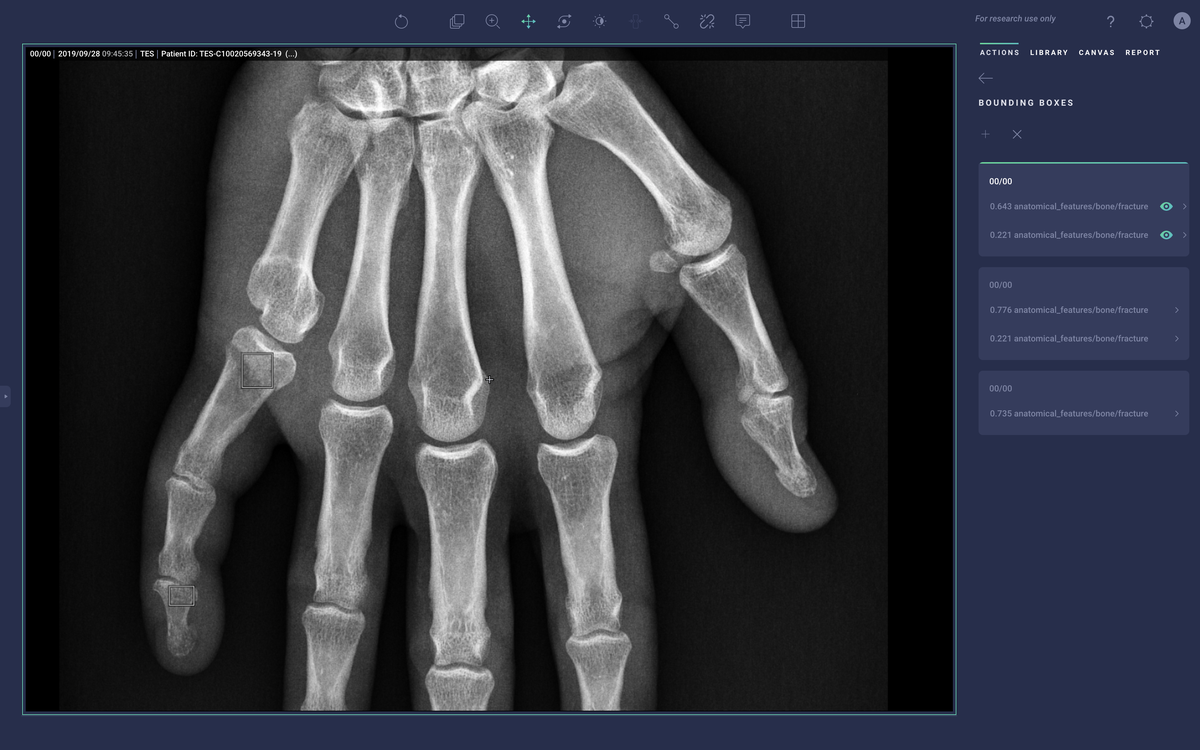

Nearly all types of currently approved AI products represent this type of solution. The very first FDA approved AI device, Cardio DL, is itself marketed as a virtual assistant and much of Arterys' product development work focuses on creating a platform to manage such assistants.

New products that have been released since Cardio DL such as Lung AI, Chest|MSK AI, and Neuro AI provide similar diagnostic support as qXR and LUnit, but couple with workflow automation that comes via integration with the Radiology Information System (RIS), PACS, electronic medical record (EMR), and dictation system. They process DICOM data to generate labels, annotations, heatmaps, and bounding boxes around regions of suspected illness. They then push those labels into the medical IT infrastructure to help prioritize the review of studies that may have abnormal findings and emphasize aspects of the study that may be concerning.